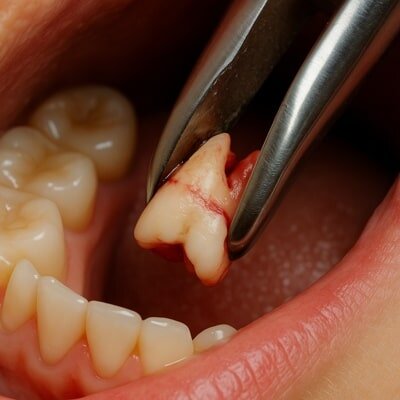

دندان عقل نهفته با دندان عقل معمولی تفاوت زیادی در روش درمان و در نتیجه هزینه دارد. در حالت نهفته، دندان زیر لثه یا داخل استخوان فک قرار دارد و برای خارج کردن آن نیاز به کشیدن دندان عقل جراحی، برش لثه، استفاده از ابزار تخصصی و بخیه وجود دارد.

همین مراحل باعث میشود هزینه کشیدن دندان عقل نهفته معمولاً بین ۲ تا ۳ میلیون تومان باشد.

در مقابل، کشیدن دندان عقل معمولی یا رویشیافته معمولاً سادهتر است و اغلب با بیحسی موضعی و بدون جراحی انجام میشود؛ بنابراین هزینهای در حدود ۱ تا ۱٫۵ میلیون تومان دارد. تفاوت قیمت در واقع ناشی از زمان بیشتر جراحی، نیاز به تجهیزات پیشرفته و مهارت جراح فک و دهان است.